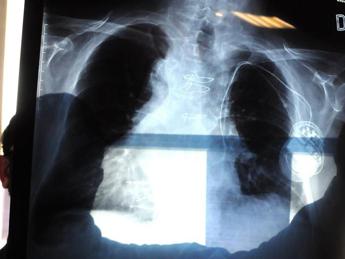

Cancro ai polmoni, individuato il punto debole: è nel ‘motore’ che lo fa crescere

(Adnkronos) – Un punto debole nel 'motore' che fa crescere il cancro ai polmoni. Un tallone d'Achille da colpire, che potrebbe diventare un bersaglio per trattamenti più efficaci. Lo ha identificato un team di scienziati del Regno Unito in un'interfaccia cruciale per una proteina che guida l'avanzare del tumore. Si tratta di Egfr (recettore per il fattore di crescita dell'epidermide), ed è una proteina con un ruolo di 'quadro' nell'organigramma del cancro: si trova sulla superficie cellulare e riceve segnali molecolari che dicono alla cellula di crescere e dividersi. Insomma, una funzione di raccordo preziosa per la malattia. In alcuni tipi di cancro, infatti, l'Egfr mutato stimola la crescita incontrollata, provocando tumori. Lo studio, condotto dalla Central Laser Facility (Clf) del Science and Technology Facilities Council (Stfc) britannico, è stato pubblicato su 'Nature Communication' e ha utilizzato tecniche avanzate di laser imaging per identificare i dettagli strutturali della proteina mutata, che l'aiutano a eludere i farmaci. E infatti ci sono vari trattamenti anticancro che bloccano e inibiscono l'Egfr mutante con l'obiettivo di prevenire la formazione tumorale, ma sono limitati perché alla fine le cellule cancerose sviluppano comunemente ulteriori mutazioni dell'Egfr resistenti al trattamento. La ricerca, evidenziano gli autori, pone le basi per ulteriori studi futuri con l'obiettivo di sviluppare terapie antitumorali di più lunga durata. Finora, non era stato compreso esattamente come le mutazioni dell'Egfr resistenti ai farmaci determinassero la crescita del tumore, ostacolando la nostra capacità di sviluppare trattamenti mirati. Gli scienziati sono andati a fondo, partendo dalle immagini ad alta risoluzione di una mutazione Egfr resistente ai farmaci nota per contribuire alla crescita del cancro ai polmoni. Per ottenere queste immagini è stata sviluppata una tecnica super avanzata ad hoc, nome in codice 'FLImP'. L'analisi ha rivelato dettagli strutturali piccoli fino a due nanometri e ha mostrato per la prima volta con precisione da record come interagiscono le molecole nella mutazione Egfr resistente. Ulteriori analisi di un gruppo dell'Università di Ginevra (Unige) hanno utilizzato simulazioni computerizzate avanzate che, combinate con l'analisi Flimp, sono state in grado di fornire ulteriori dettagli. Confrontando l'Egfr mutato e quello sano gli scienziati hanno identificato le interfacce tra le molecole che interagivano nella mutazione resistente. "La scoperta è il culmine di anni di ricerca e sviluppo tecnologico. Se questa interfaccia si rivelasse un bersaglio terapeutico efficace, potrebbe fornire un approccio completamente nuovo allo sviluppo farmaceutico tanto necessario", commenta Marisa Martin-Fernandez, leader dell'Octopus Group del Clf, che ha condotto lo studio. Il team ha fatto degli esperimenti per approfondire il meccanismo messo nel mirino: prima in cellule polmonari in coltura e poi nei topi, gli esperti hanno introdotto ulteriori mutazioni nell'Egfr resistente ai farmaci, che interferivano con le interfacce appena scoperte. In questi test è stato dimostrato che una delle mutazioni aggiuntive bloccava la crescita del cancro, facendo sì che i topi non sviluppassero tumori. Un risultato che indica ulteriormente come la capacità di Egfr mutato di promuovere il cancro dipenda effettivamente da queste interfacce. La ricerca dimostra anche "il potere dell'imaging per comprendere meglio il funzionamento interno del cancro", fa notare Gilbert Fruhwirth, leader del gruppo Imaging Therapies and Cancer del King's College di Londra che ha convalidato i risultati sugli animali. Ora i ricercatori sperano che queste interfacce possano fungere da potenziali bersagli per nuove terapie in grado di superare la resistenza acquisita dalle mutazioni dell'Egfr. "Questa svolta è stata resa possibile da una combinazione di simulazioni all'avanguardia e tecniche sperimentali che ora possono 'visualizzare'" le dinamiche del tumore "con un dettaglio senza precedenti”, osserva Francesco Luigi Gervasio (Unige). La risoluzione del microscopio è stata spinta "oltre i limiti dell'immaginazione", aggiunge Yiannis Galdadas (Unige), che ha eseguito le simulazioni. "È quasi possibile 'toccare' il sito della mutazione e vederne l'effetto", racconta. In ulteriori studi in corso al Clf si sta testando il metodo di ricerca su altre mutazioni dell'Egfr note anch'essere per contribuire al cancro del polmone. Obiettivo stabilire se c'è un eventuale ruolo di questa interfaccia nello sviluppo di altri tumori, compreso il cancro al cervello. —cronacawebinfo@adnkronos.com (Web Info)